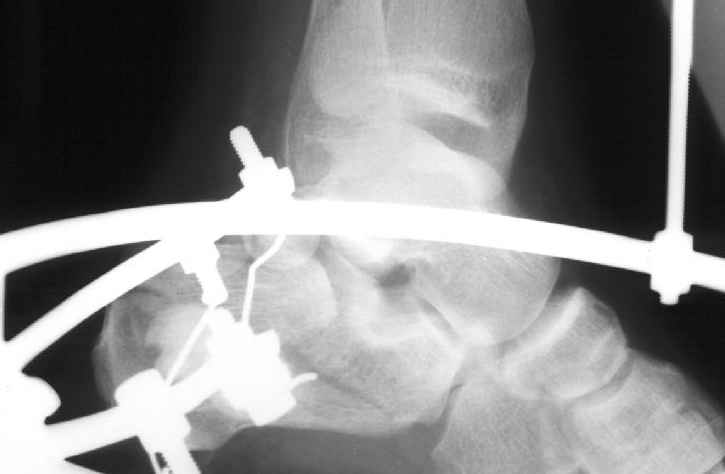

Накладываем спицевой дистрактор, позволяющий выхаживать м/ткани и одновременно устранять захождение отломков.